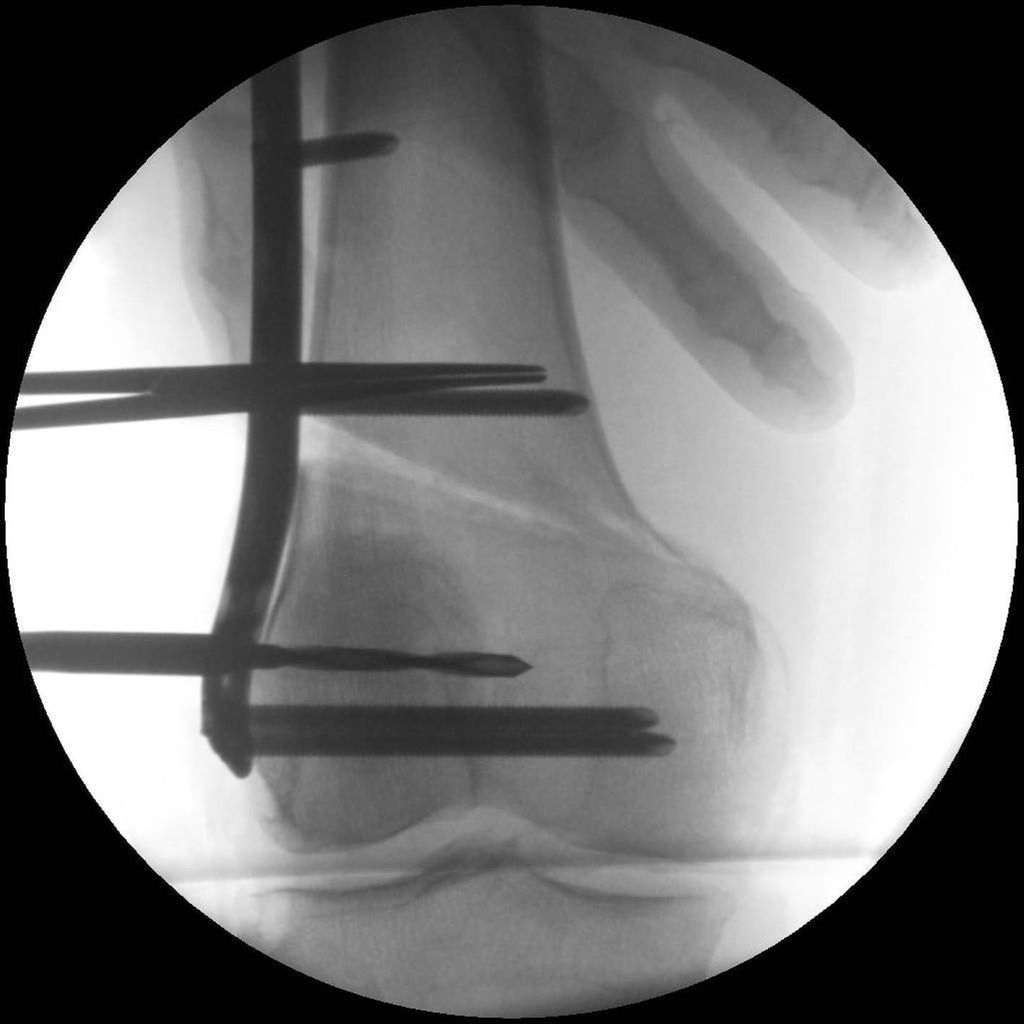

17-jähriger Patient mit wiederkehrenden Patellaluxationen

Aufgrund eines erhöhten Caton-Deschamps-Index von >1,2 erfolgten die Tuberositasdistalisierung und die MPFL-Plastik mit der Gracillissehne (Abb. 2 und 3). Ca. 4 Wochen nach dem operativen Eingriff stürzte der Patient auf das rechte Kniegelenk mit Mehrfragmentbruch des Tuberositasfragments (Abb. 4). Die neuerliche Fixierung erfolgte mittels 3,5mm-Drittelrohrverplattung sowie, wegen des Mehrfragmentbruches im proximalen Bereich, mittels Durchflechtungsnaht und Knochenankern (Abb. 5).

Abb. 5: Intraoperatives Bild nach Verplattung und Zügelung mittels Durchflechtungsnaht und Knochenankern